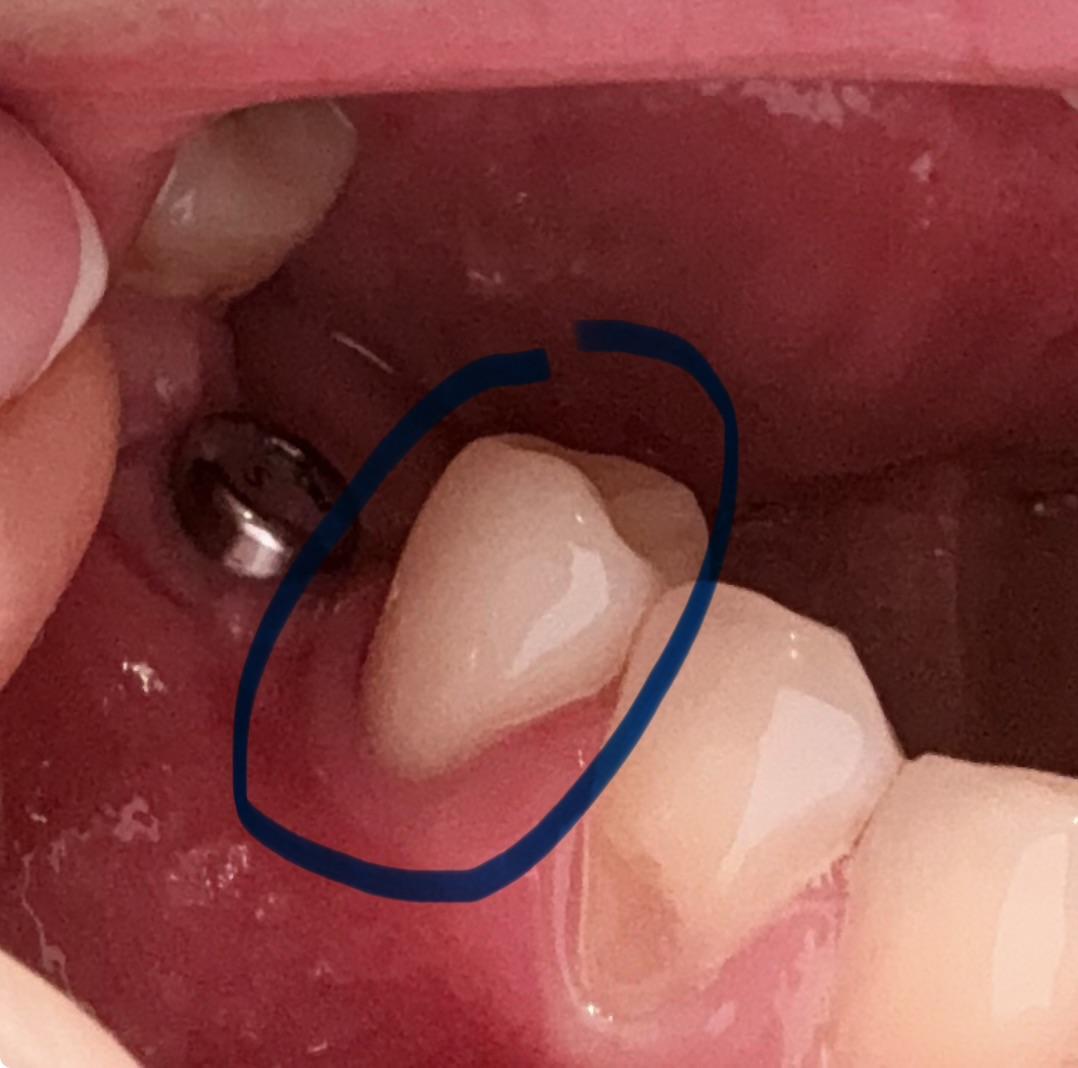

Вечером решила дома рассмотреть все внимательно и увидела, что с внутренней стороны есть небольшой зазор (1 мм примерно на вскидку). Не понимаю как врач этого не мог заметить?! Такое возможно? Или надеялся что я не увижу и потом скажут это у вас десна опустилась из за импланта.

Вот читаю, что так не должно быть. Плюс у меня соседний стоит имплант 3 недели и переживаю что десна еще опустится.

Нужно ли переделывать или подождать? И как это все переделывается если необходимо. И в чем может быть причина?

Фото прикладываю.